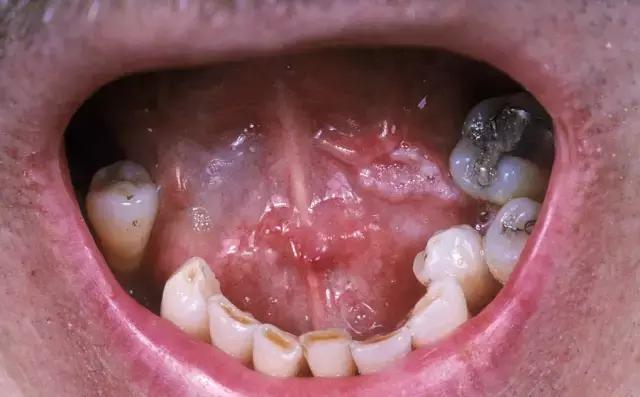

舌癌的经口楔形切除术

下颌骨分段切除术

下颌骨切除术

口腔癌手术路径图

舌是参与发音、咀嚼和进食的主要器官,舌癌扩大切除时,一般会损伤这些功能,给患者带来巨大的痛苦。颌骨切除的患者,面孔外观也会发生塌陷。因此,在手术中的修复和手术后的舌功能康复训练、口腔护理和营养支持都是非常重要的。可以说,要对抗舌癌这种“凶险恶症”,需要患者和医护人员都付出很大的耐心和勇气。